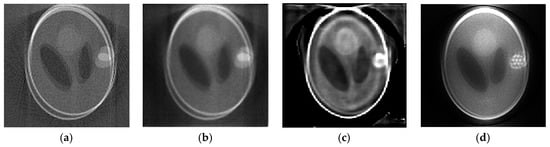

3.1. Numerical Phantom Experiments

3.2. Head Phantom Experiments